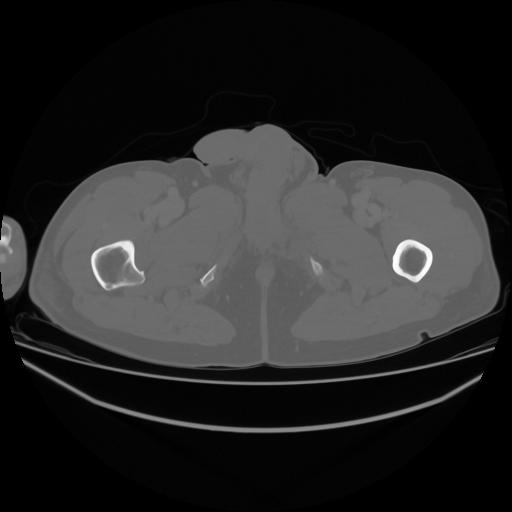

5 CUERPO,CE,Vol,1.0,CUERPO,,